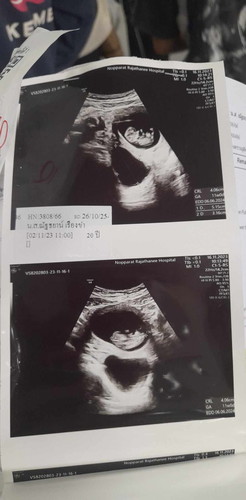

ตั้งครรภ์ได้12วีคค่ะเเล้วไปซาวเจอถุงน้ำในมดลูกเเม่ใช้บัตร30ค่ะ

เเม่ๆคนอื่นที่ซาวเจอถุงน้ำเเบบนี้หมอจะซาวให้บ่อยกว่าเดิมมั้ยค่ะพอดีว่าเป็นห่วงลูกมากเลยค่ะกลัวจนเครียดวิตกไปหมดเลยค่ะโรงบาลนพรัตค่ะ

ก้อนกี่ เซ็นคะ แม่. เราก็เป็นนะน่าจะมาพร้อมกับลูกเลยเพราะรู้สึกเหมือนเป็นก้อนตอนอาการคล้ายท้องเลยตรวจก็ท้องจริงๆแต่ก้อน1ซม ไม่ใหญ่ไม่มีอะไรในนั้นเป็นแค่ซีสธรรมดาคุณหมอบอกท้องโตเดี๋ยวคงสลายไปเองอาจเป็นเพราะฮอโมนตั้งครรภ์ด้วยค่ะ